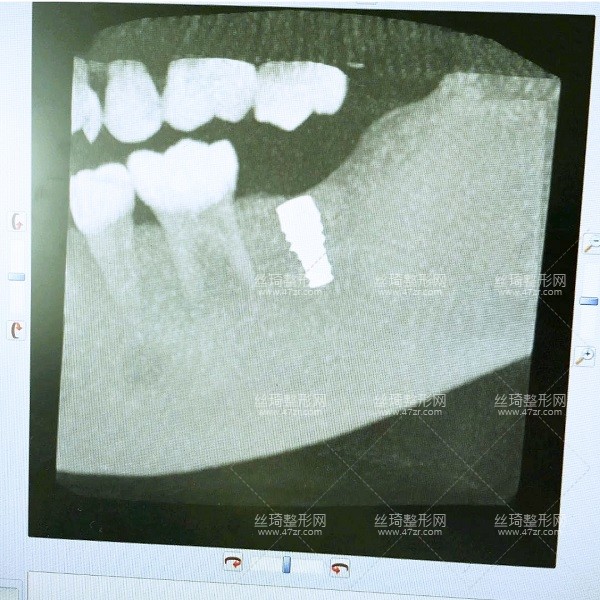

2.種植牙案例

手術(shù)第1天

一直不知道什么原因?qū)е挛业难罆?huì)這樣,多方咨詢之后選擇了長(zhǎng)沙中諾口腔進(jìn)行整牙,過(guò)去檢查了一下,醫(yī)生說(shuō)我可以搞種植牙,但是以前補(bǔ)過(guò)的牙現(xiàn)在顏色變了,需要重新做,看來(lái)是個(gè)大工程啊,啊啊啊啊~~~

手術(shù)第2天

今天過(guò)來(lái)醫(yī)生檢查了我的牙床和骨組織,情況不錯(cuò),可以直接調(diào)節(jié)。首先助理幫我清潔口腔,護(hù)士準(zhǔn)備手術(shù)室,清理過(guò)口腔后,吃了止痛藥,然后進(jìn)手術(shù)室,然后躺到牙椅上,就打麻藥的時(shí)候有點(diǎn)緊張,種牙很輕松,全程一個(gè)半小時(shí)。出來(lái)后,冰敷了,告訴我注意事項(xiàng),讓我一周后來(lái)拆線。

手術(shù)第8天

較近刷視頻看到很多美食,但是現(xiàn)在與我無(wú)緣啊,多么痛的領(lǐng)悟~今天拆線,然后看看后面的牙啥時(shí)候弄。牙醫(yī)說(shuō)我恢復(fù)的不錯(cuò),但還是要養(yǎng),下周再過(guò)來(lái)檢查牙周,種植牙的牙冠要等那個(gè)釘修復(fù)好了再帶,要好幾個(gè)月,今天就到這里。